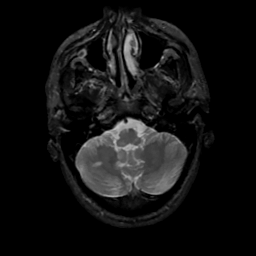

MR Study #10, April 28, 1991 -- Slice #9